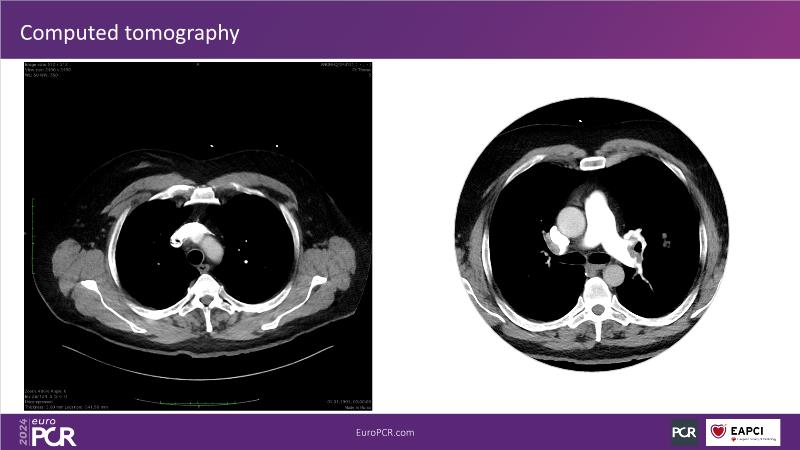

Why mechanical thrombectomy should be considered in the management of acute pulmonary embolism

In this EuroPCR 2024 session, study the case of a patient with high-risk pulmonary embolism and another with intermediate to high-risk pulmonary embolism, delve into discussions on clinical evidence for mechanical thrombectomy in pulmonary embolism, acquire skills to evaluate eligibility for mechanical thrombectomy, and learn how to integrate such technique in local pulmonary embolism patient pathway.